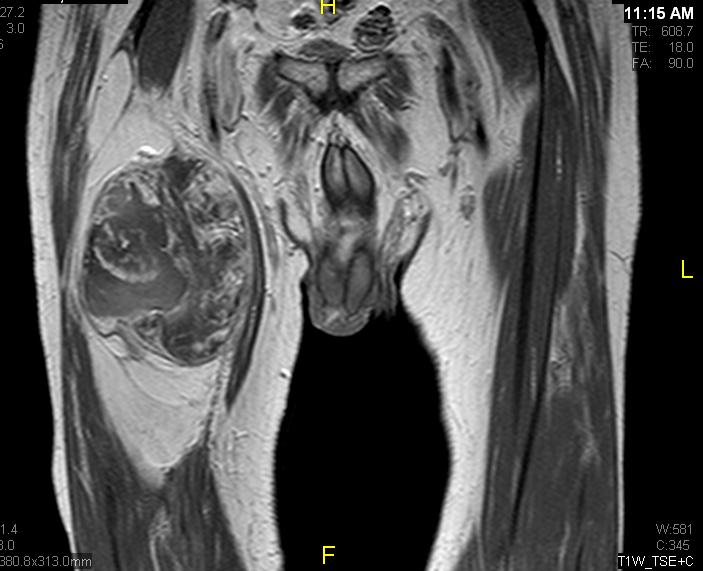

Fig. 1 & 2 Magnetic Resonance Image shows a large heterogeneous mass in the left gluteal region with low intensity signal on Axial (Fig. 1) and Coronal (Fig. 2) T1-weighted images admixed with some high signal areas indicative of fatty tissue. Higher intensity signal is visible compatible with hemorrhage or necrotic tissue. The mass involve the central portion of the left iliac bone.

Axial (Fig. 4) and Coronal (Fig. 5) contrasted T1-weighted MR images show a large heterogeneous mass with central and peripheral enhancement. Central low signal intensity image is compatible with necrosis and hemorrhage.